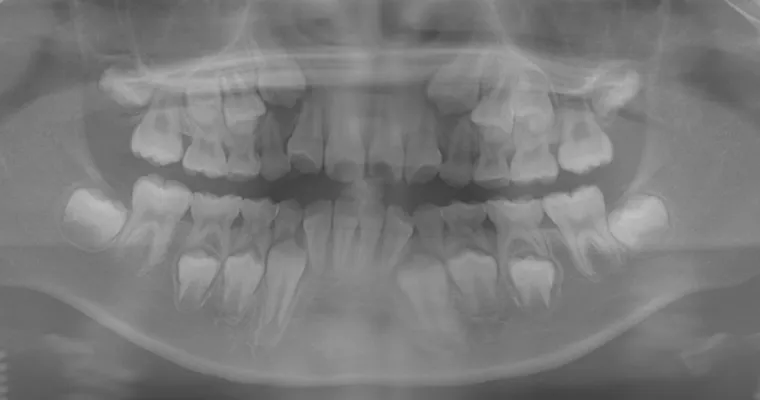

治療前 パノラマレントゲン

治療前 セファロレントゲン

| 主訴 | 幼少期から反対咬合 |

|---|---|

| 治療期間 | 10ヶ月 |

| 治療費 | 440,000円(税込) ※調整、器具、治療後にお渡しするEFLine(矯正後の後戻りを防ぐ器具)も全て込みでの金額となっております。 |

| 治療内容 | 6歳で上下拡大 上顎牽引装置 EF Lineで筋機能療法 |